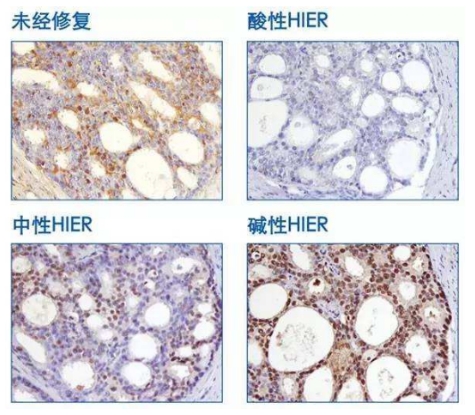

1 Impact of pH value: Staining intensity varies with different tissues and antigen retrieval solutions of different pH values.

P27 staining of prostate tissue with antigen retrieval performed at 95°C for 10 minutes.

1 Common antigen retrieval buffers include citrate buffer (pH 6.0), EDTA buffer (pH 8.0–9.0), Tris/Tris-EDTA buffer (pH 9.0–10.0), and trypsin method (pH 3.5 ± 0.2).

2 The pH value of the retrieval buffer has a significant impact on staining results, and there is no universal antigen retrieval buffer.

3 Most antigens can achieve optimal retrieval effects in buffers with a pH range of 8.0–9.0; therefore, alkaline buffers are more widely used.